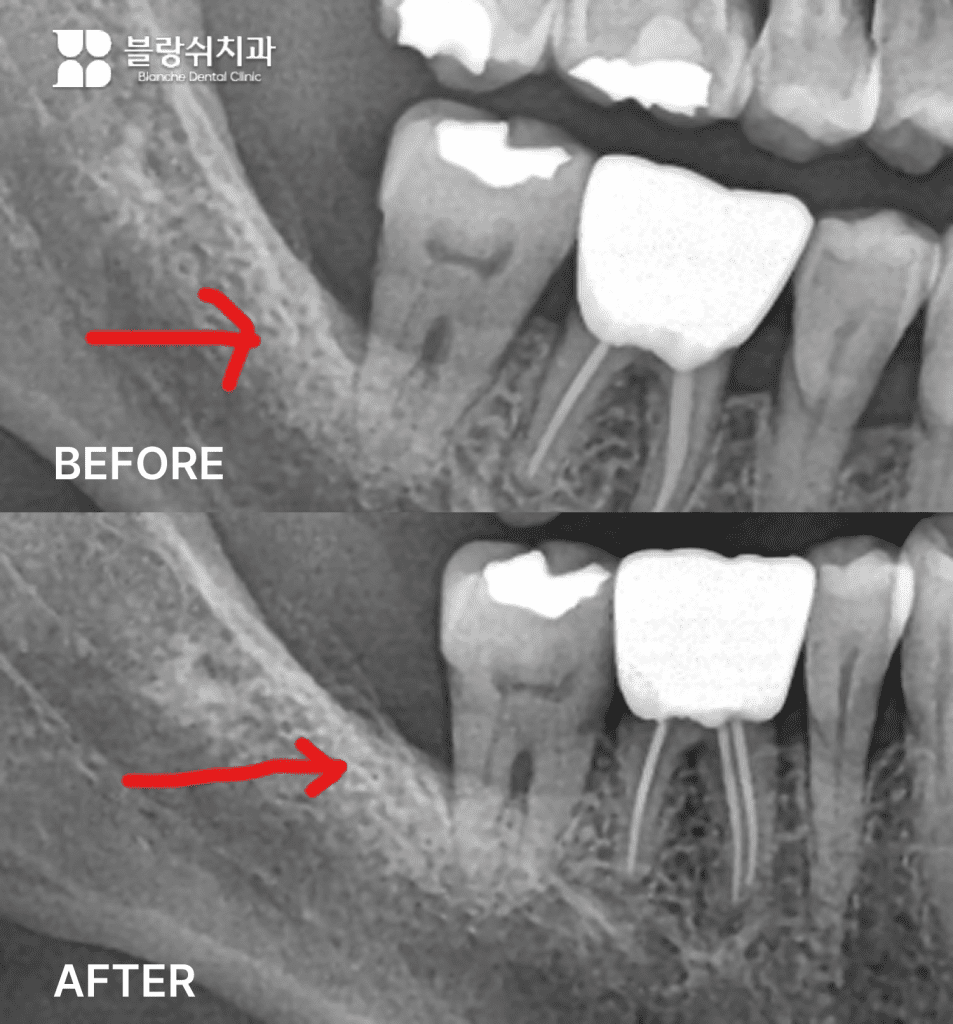

• 진단: 하악 대구치 부위에서 3벽성 골손실이 확인되었습니다.

• 판단 포인트: 흔들린다고 항상 발치가 정답은 아닙니다. 뼈가 녹은 부위에 벽이 3면 이상 남아 있으면 재생의 틀이 만들어집니다. 이 구조가 있어야 엠도게인이 작용할 가능성이 커집니다. 이 환자분의 케이스입니다.

• 치료: 전반적 잇몸치료 + 엠도게인 병행으로 진행했습니다.

• 결과: 6개월 후(2023년 10월 → 2024년 4월) 엑스레이에서 뼈가 차오른 것을 확인했습니다.